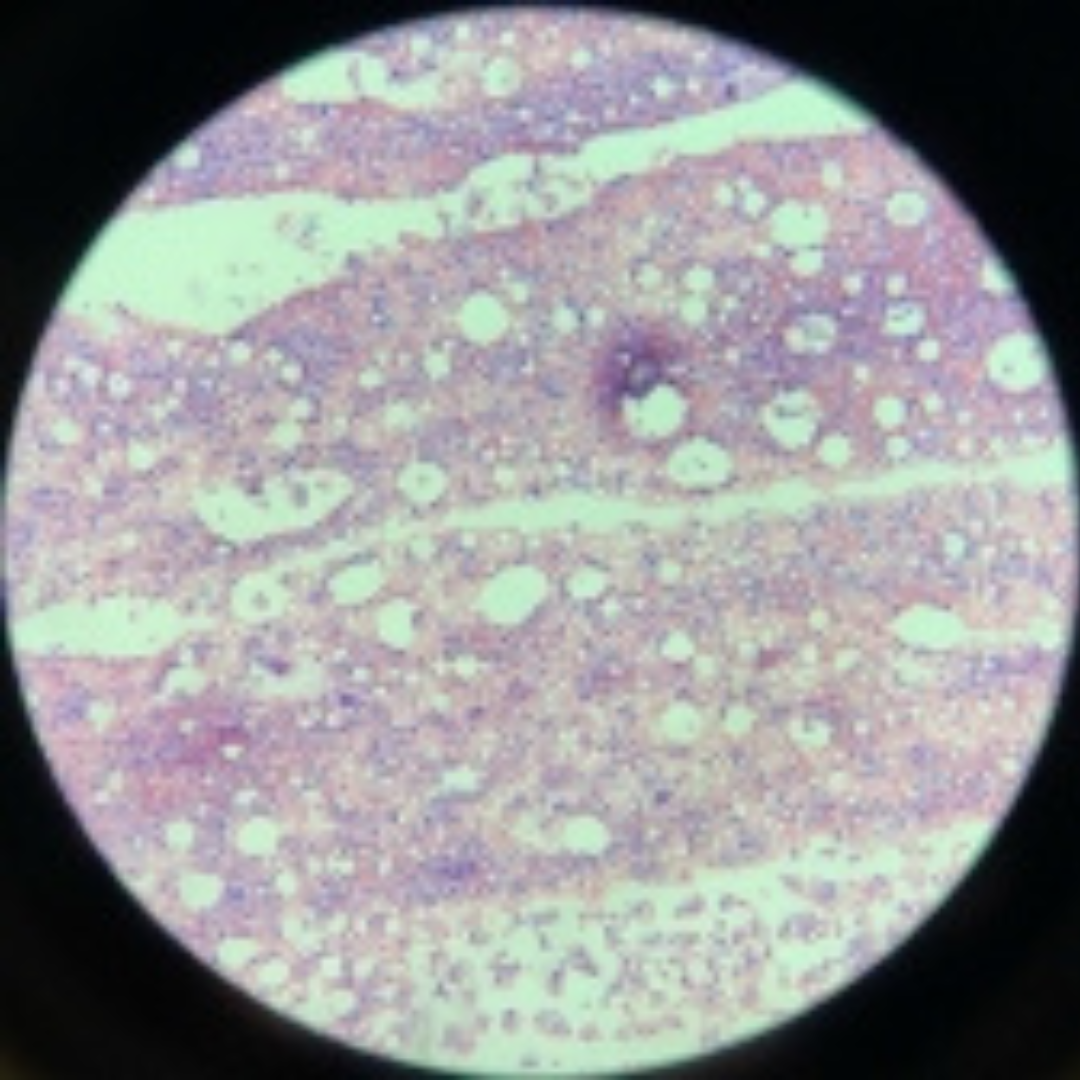

7

New cards

Bone Marrow

8

New cards

Bone Marrow

9

New cards

Bone Marrow